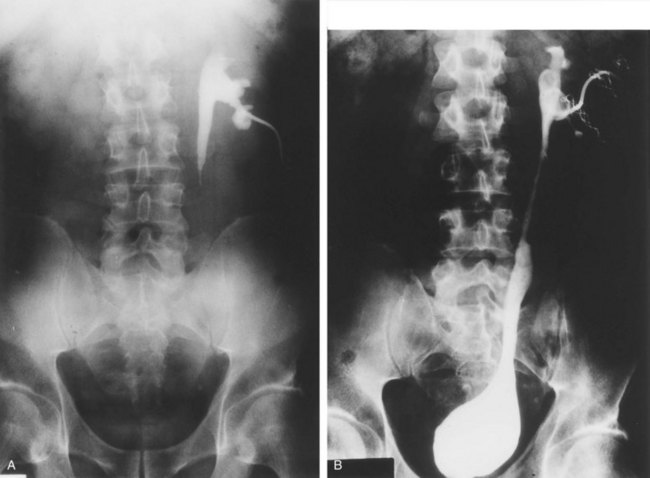

UPJ obstruction, although most often a congenital problem, can present clinically at any time of life. Historically, the most common presentation in neonates and infants was the finding of a palpable flank mass. However, the current widespread use of maternal, prenatal ultrasonography has led to a dramatic increase in the number of asymptomatic newborns being diagnosed with hydronephrosis, many of whom are subsequently found to have UPJ obstruction (Bernstein et al, 1988; Wolpert et al, 1989). A fraction of cases may also be found during evaluation of azotemia, which may result from bilateral obstruction in a functionally or anatomically solitary kidney. UPJ obstruction may also be incidentally found during studies performed to evaluate unrelated anomalies such as congenital heart disease (Roth and Gonzales, 1983). In older children or adults, intermittent abdominal or flank pain, at times associated with nausea or vomiting, is a frequent presenting symptom. Hematuria, either spontaneous or associated with otherwise relatively minor trauma, may also be an initial symptom. Laboratory findings of microhematuria, pyuria, or frank urinary tract infection might also bring an otherwise asymptomatic patient to the urologist. Rarely, hypertension may be a presenting finding (Riehle and Vaughan, 1981). Radiographic studies should be performed with a goal of determining both the anatomic site and the functional significance of an apparent obstruction. Although excretory urography remains a reasonable option for radiographic diagnosis, this study is less commonly used today. Classically, excretory urographic findings include delay in function associated with a dilated pelvicalyceal system. If the ureter is visualized, it should be of normal caliber. In some patients, symptoms may be intermittent and urography between painful episodes may be normal. In such cases the study should be repeated during an acute episode when the patient is symptomatic (Nesbit, 1956). Provocative testing with diuretic urography may allow accurate diagnosis in select cases. The patient should be well hydrated and the study then performed after injecting furosemide, 0.3 to 0.5 mg/kg (Malek, 1983) (Fig. 41–2).

Figure 41–2 A, This patient with intermittent left flank pain underwent intravenous urography. The calyces are sharp bilaterally without evidence of obstruction. However, there is a “box-shaped” pelvis on the left side, which may be associated with intermittent obstruction. B, This intravenous urogram in the same patient was performed along with injection of intravenous furosemide, which brought out the obvious left-sided ureteropelvic junction obstruction. The patient’s symptoms were subsequently relieved with a left pyeloplasty.